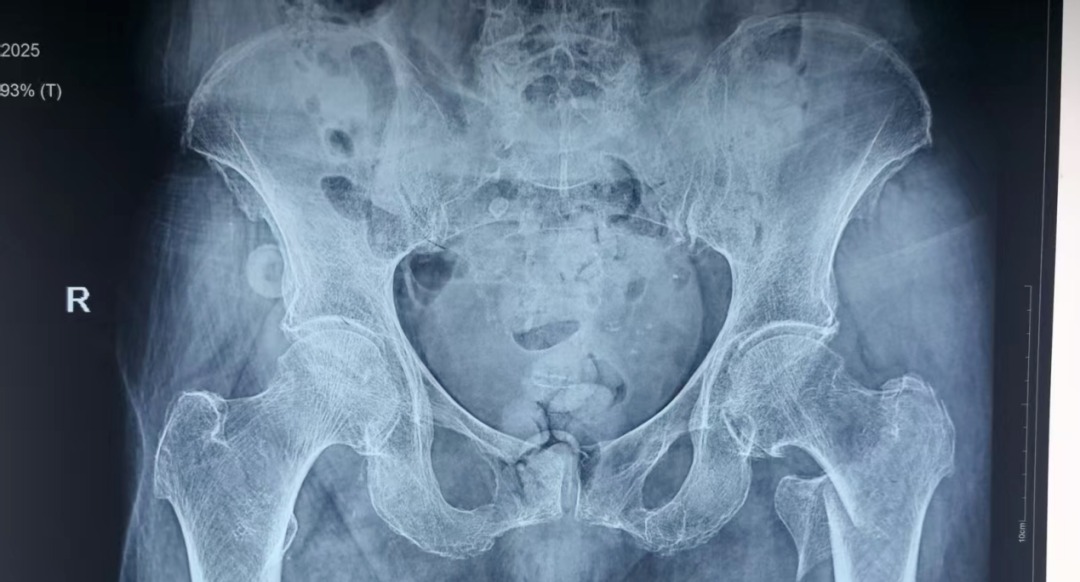

为防止坠积性肺炎、褥疮、深静脉血栓等并发症发生,杨自权主任团队在患者入院后,积极完善术前准备,经过医务处的组织和血管外科、麻醉科、康复科等多学科的MDT合作,手术时间定于患者入院第三天。2022年,美国AAOS(美国骨科医师协会)指南强烈推荐老年股骨转子间骨折(稳定或不稳定)采用髓内钉内固定。因此,杨自权主任团队拟行股骨转子间骨折闭合复位髓内钉内固定微创手术。

手术当日,杨自权主任团队借助丰富的手术经验,术前在牵引床、G臂辅助下迅速给予患者闭合复位骨折断端,结合经典的“2-1-1”微创手术切口实施手术,手术过程顺利,G臂透视可见骨折复位满意,髓内钉位置满意。术后患者顺利出院,安返家中。